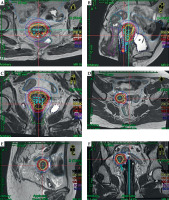

Fig. 6

Dose distribution for the two patients. A) Transverse, B) sagittal, and C) coronal sections of patient No. 1; D) transverse, E) sagittal, and F) coronal sections of patient No. 2

Two patients underwent a treatment regimen consisting of EBRT with concurrent chemotherapy combined with MR-IGBT. The EBRT was delivered in 25 fractions over a total dose of 45 Gy. The MR-IGBT was administered in four fractions with a total dose of 28 Gy, utilizing two fractions per application with a 12-hour interval between them. During the actual treatment, the patients were under general anesthesia and real-time guidance of trans-rectal ultrasound was followed according to the pre-determined treatment plan. Gradual insertion of the needles into the tumors was carried out during the procedure. Afterwards, MR imaging was done with the applicator in situ to perform the actual treatment planning. Both patients exhibited conformal dose distribution, as depicted in Figure 6. Doses delivered to the target volume and organs at risk (OARs) of both patients met dose constraints specified in the EMBRACE II guidelines, as outlined in Table 1. Currently, at the time of writing the manuscript, patient No. 1 has been followed up for 15 months, while patient No. 2 has been followed up for 18 months. Both patients have shown complete response to the treatment, with no evidence of tumor recurrence. Additionally, there have been no significant reports of acute or long-term toxicities.